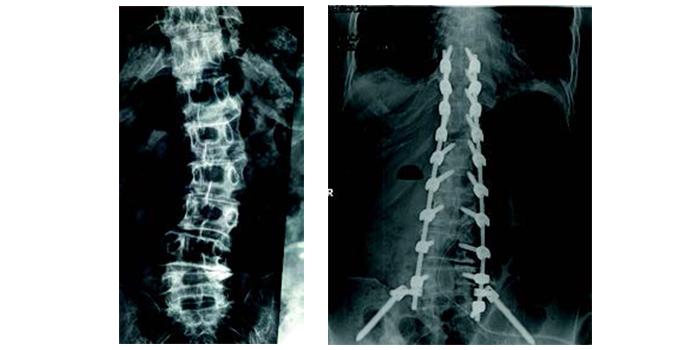

Για πρώτη φορά στην Ελλάδα, το 2016, εφαρμόστηκε με επιτυχία στο Metropolitan Hospital το σύστημα 3D απεικόνισης/χειρουργικής πλοήγησης σε παιδιά με σκολίωση.

Το σύστημα επέτρεψε την τοποθέτηση των εμφυτευμάτων σε πραγματικό χρόνο με την ακρίβεια αξονικού τομογράφου. Η ακρίβεια αυτή εκμηδενίζει την πιθανότητα ιατρικού λάθους και την πρόκληση μόνιμων νευρολογικών βλαβών, ενώ παράλληλα παρέχει ένα εξαιρετικό αισθητικό αποτέλεσμα, πράγμα σημαντικό για τις κοπέλες που πάσχουν από σκολίωση. Το σύστημα χρησιμοποιείται σε παιδιά και ενήλικες με κύφωση ή σκολίωση.

Για τα παιδιά και τους εφήβους, η χειρουργική αντιμετώπιση της σκολίωσης προτείνεται για καμπύλες που έχουν ξεπεράσει τις 45 μοίρες. Στην περίπτωση που σκολιώσεις αυτού του μεγέθους αφεθούν χωρίς χειρουργική αντιμετώπιση θα συνεχίσουν να επιδεινώνoνται ακόμη και μετά την ολοκλήρωση της σκελετικής ωρίμανσης, με αποτέλεσμα το χρόνιο πόνο, την αναπνευστική δυσλειτουργία και τις ψυχοκοινωνικές επιπτώσεις, ιδιαίτερα για τα κορίτσια. Δυστυχώς, όταν η σκολίωση ξεπεράσει τις 45 μοίρες ο κηδεμόνας δεν είναι πλέον αποτελεσματικός. Για έναν έφηβο με κύφωση Scheuermann, εάν η κύφωση συνεχίζει να εξελίσσεται φτάνοντας τις 70 μοίρες παρά τη χρήση του κηδεμόνα και το παιδί παραπονείται για συνοδό πόνο, η χειρουργική επέμβαση αποτελεί τη θεραπεία εκλογής.

Η αντιμετώπιση στους ενήλικους είναι κατά κανόνα χειρουργική. Διαδερμικές και αναίμακτες επεμβάσεις μπορούν να βοηθήσουν στη διόρθωση της κύφωσης και την αντιμετώπιση του πόνου ενός οστεοπορωτικού κατάγματος. Η σκολίωση των ενηλίκων θα πρέπει να διορθωθεί χειρουργικά όταν συνδυάζεται με πόνο στη μέση ή στα πόδια, που περιορίζει τις καθημερινές δραστηριότητες και μειώνει την ποιότητα ζωής.